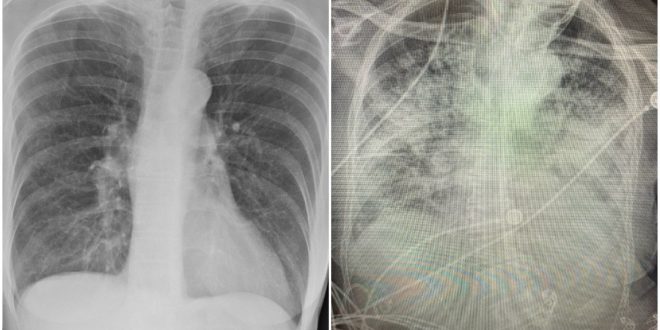

En radiografías presentadas por la doctora Bankhead-Kendall se puede ver que los pulmones sanos tienen una gran parte de color negro, lo cual principalmente es aire. En los rayos X de personas fumadoras se pueden ver líneas blancas, estas indican cicatrización y congestión; mientras que en las de una persona que padeció COVID-19 el color que predomina es el blanco

Scroll: 1) Healthy 2) Smokers 3) COVID pic.twitter.com/Iu9V8OrpnK